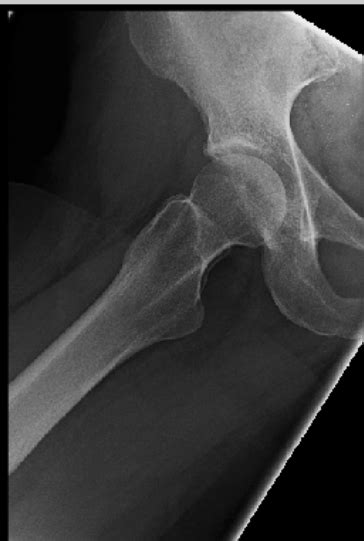

Before we get into the nitty-gritty of muscles, let’s give a shout-out to the hip joint itself. This incredible ball-and-socket joint is a true masterpiece of biomechanical design, allowing for a huge range of motion. It’s formed by the head of the femur (your thigh bone) fitting snugly into the acetabulum, a deep socket in your pelvis. This structure is what gives our hips the versatility to move in pretty much any direction. But with great range comes great responsibility – we need strong, coordinated muscles to control all these movements safely and effectively. Understanding the muscles that power these actions is crucial, whether you’re an athlete looking to boost performance, someone recovering from an injury, or just curious about how your body works. We’re talking about muscles that not only allow for dynamic movements but also play a vital role in stabilizing the pelvis and spine. Think about it: every step you take, every time you turn, your hip muscles are working tirelessly. Getting a grip on which muscles are involved in lateral rotation and abduction of the hip can help you better understand your body’s capabilities and limitations.